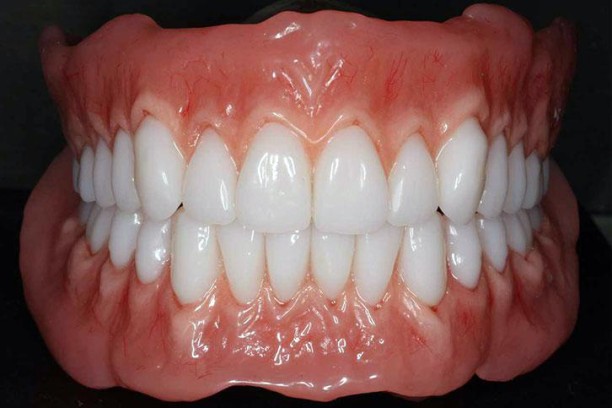

Complete Dentures

A removable dental appliance replacing all missing teeth in the upper and lower jaw restoring chewing,speach,facial support and apperance typically made of acryilic or procleain fitting over the gums with types including conventional (after healing) and immediate (right after extraction)